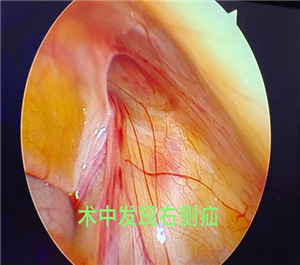

术前检查彩超及CT均提示左侧腹股沟斜疝,患者既往右侧腹股沟区也未发现可复性包块。术中发现左侧疝并网膜嵌顿,右侧腹壁下血管外侧缺损,诊断双侧腹股沟斜疝。遂行双侧疝囊高位结扎术,术后恢复良好出院。